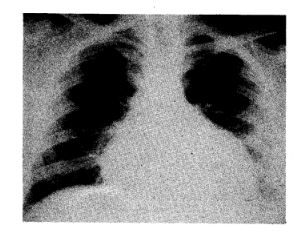

Instilación intrapericárdica de clorhidrato de tetraciclina. Un método útil para evitar la recidiva de taponamientos cardíacos de origen neoplásico